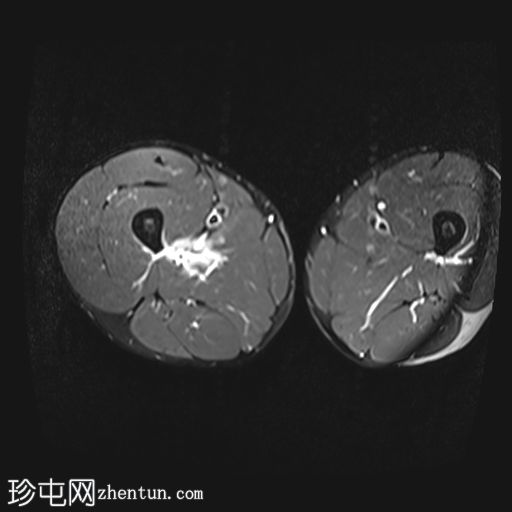

轴位

T2加权像

内收长肌和内收短肌中远侧外侧可见羽状改变和肌内水肿,主要累及内收大肌,长15厘米,宽4厘米。未见明显血肿或完全性肌纤维撕裂。

后腱膜、邻近神经血管交界处及邻近肌间隙可见积液,少量积液向外侧扩散,沿肌间隙到达大腿中远侧。

内收肌腱完整,骨性附着点清晰可见,肌腱轻度增厚,中部可见腱周水肿;未见撕裂。

影像学特征符合英国田径肌肉损伤分级(BAMIC/BAC)2B级损伤,主要累及大收肌。未见明显的血肿或肌纤维完全撕裂。

后侧腱膜、邻近神经血管束及肌间隙可见积液,少量积液沿肌间隙向外侧延伸至大腿中远端。